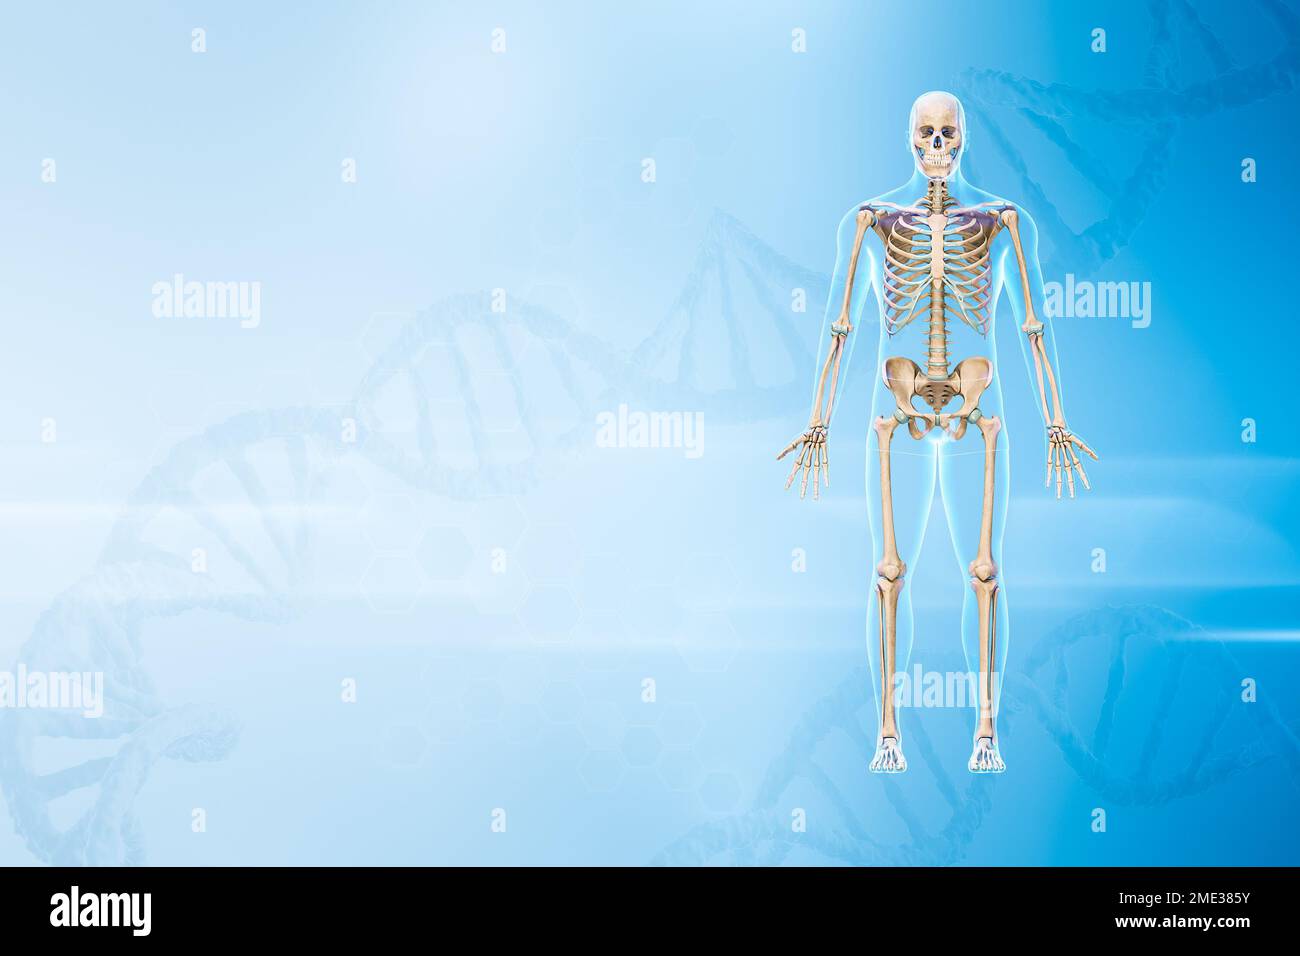

RF2ME385Y–Menschliches männliches Skelett mit Vorderansicht des Körpers 3D-Darstellung mit Kopierraum und DNA-Hintergrund. Anatomie, Medizin und Gesundheitswesen, Biologie, ich